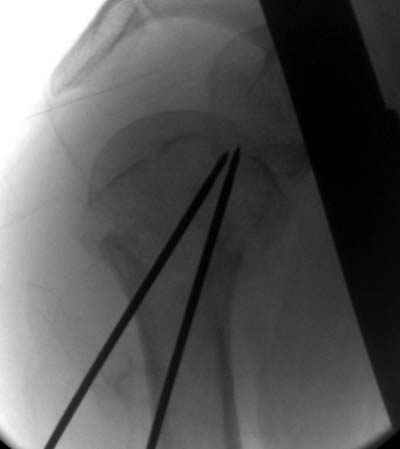

Пока я пользуюсь методикой принятой у нас (методика Сиэтла), также перкутанный спицевой метод, только сцицы 2.8 мм с резбой на конце.

Здесь случай перелома-вывиха плеча, больному 56 лет, после "дважды" закрытой неудачной репозиции, опять же ургентно взяли в операционную, после полного общего обезболивания попытались сделать репозицию, и фиксацию провели спицами.

Больной находился в повязке, примерно напоминяющей косыночную, рекомендованы движения в локтевом суставе и маятниковые движения в плече, спицы удалены в три недели (были случаи миграции)